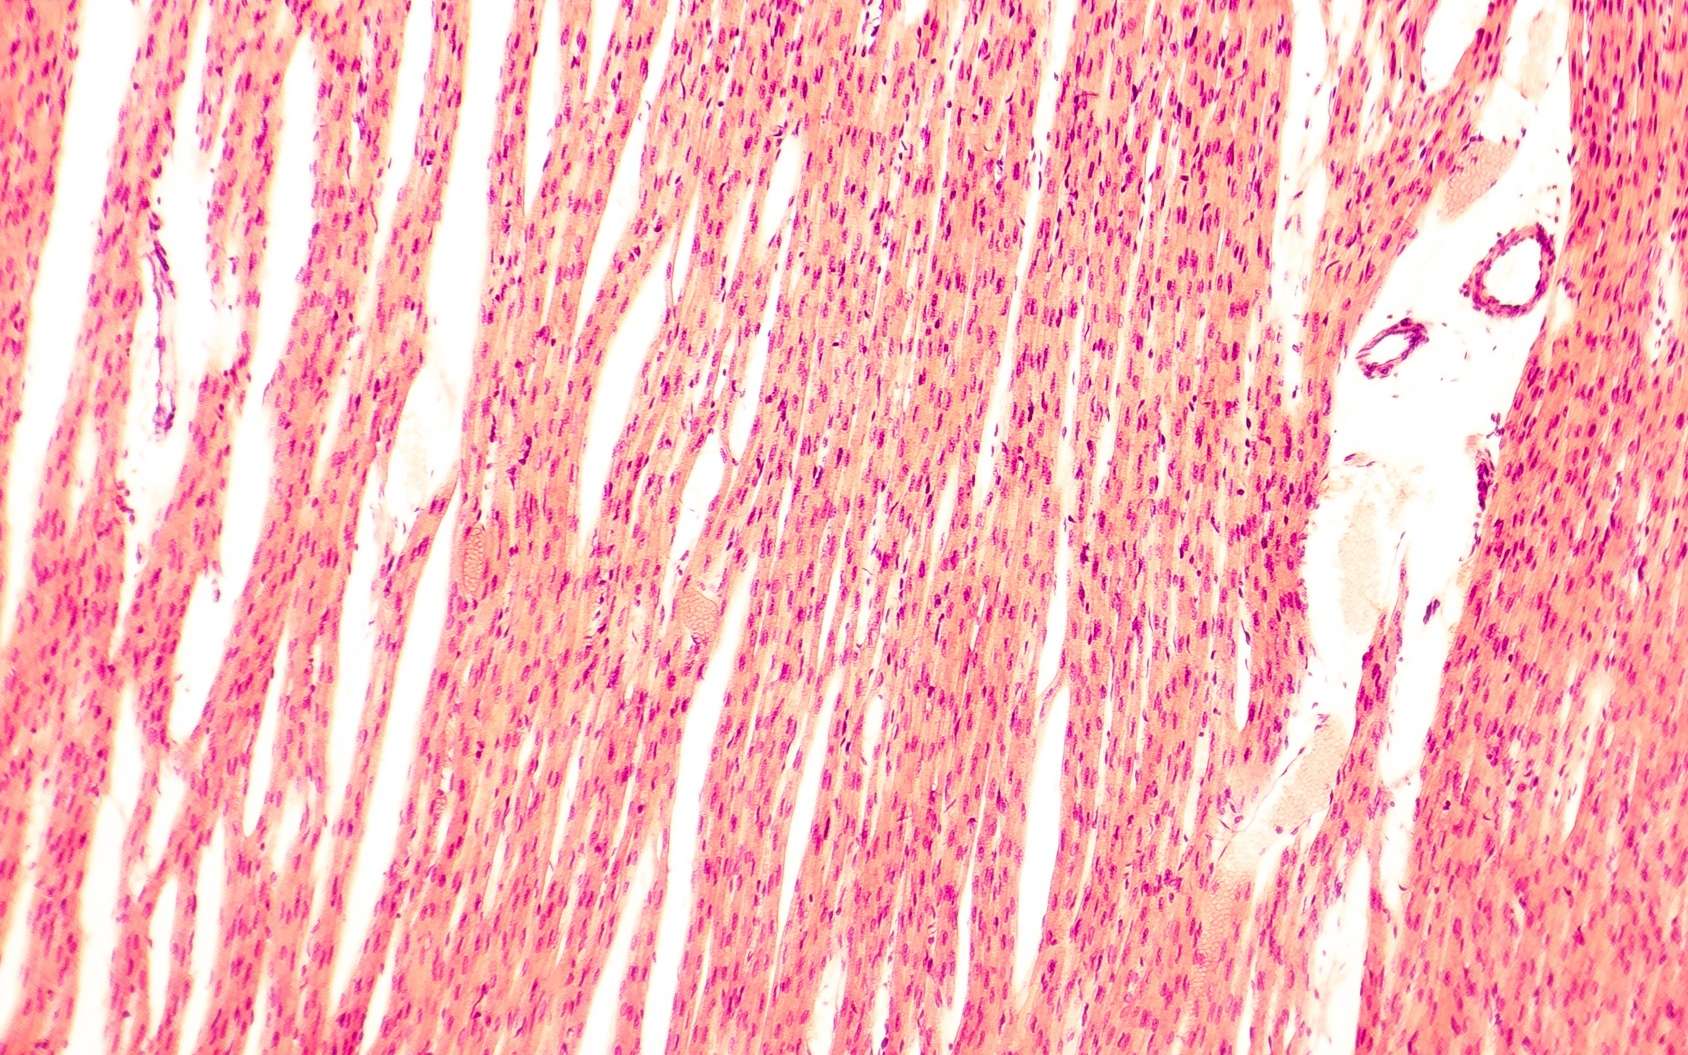

Representative photomicrographs of cardiomyocyte size stained with HE

Representative photomicrographs of cardiomyocyte size stained with HE What Does Cardiomyocyte Mean reprogrammers have checked all the right boxes, but there are differences between their respective cardiomyocytes. the fundamental contractile cell of the myocardium is the myocyte. a cardiomyocyte is the fundamental contractile cell of the heart. learn about the structure and function of cardiac myocytes, the specialized striated muscle cells that form the heart. Discover how sarcomeres,. What Does Cardiomyocyte Mean.